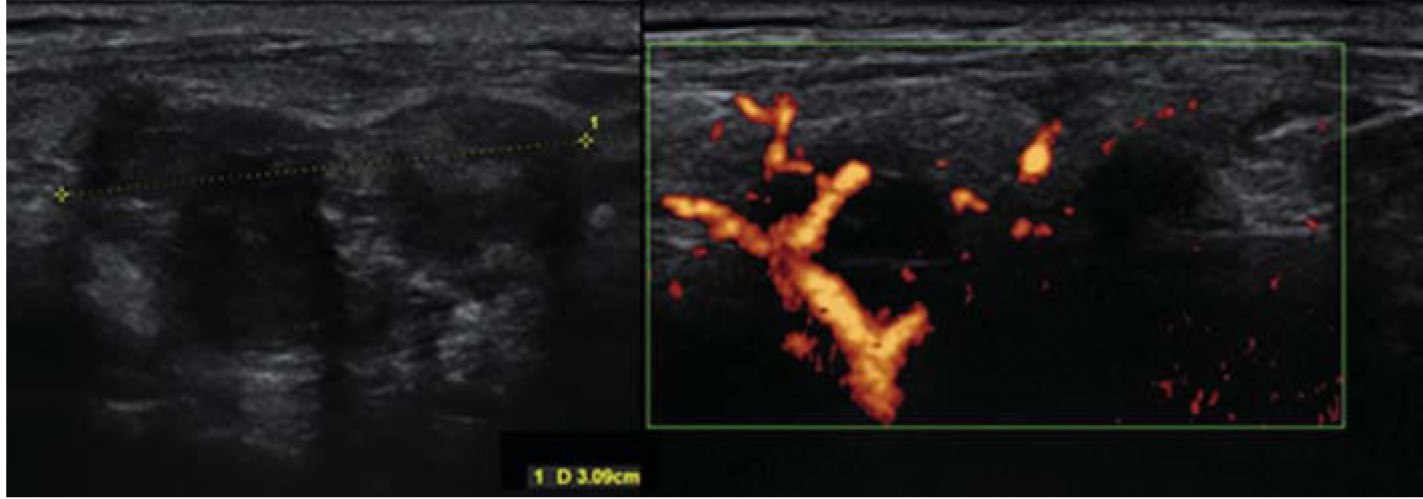

5. Fig. 4. On the left - the formation of the thyroid gland, suspicious of malignancy (> 3 cm, heterogeneous, irregular in shape with uneven edges); on the right - intensively blood supply during Doppler ultrasound imaging (images of Zakharova S.M., Research Center for Endocrinology). | |

| Subject | ||

| Type | Other | |

View

(190KB)

|

Indexing metadata ▾ | |